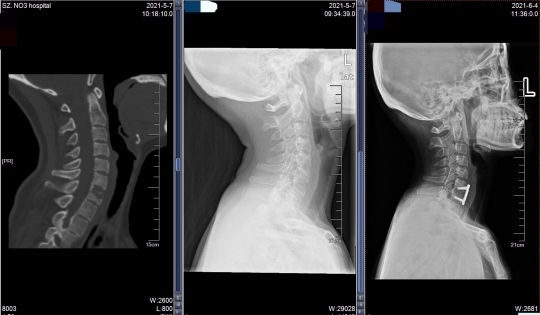

袁女士颈椎术前CT、DR及术后DR

根据袁女士的病情,相关科室经过会诊,决定对她进行手术治疗。骨二科主任李宏伟提出,要一次完成3个手术:胸椎后路固定植骨融合术、经左侧第十肋开胸胸11椎体病灶清除椎管减压植骨融合术、经前路颈7椎体结核病灶清除减压植骨钢板内固定术。

这台手术对骨科医生的技术要求很高,同时完成胸椎前后路及颈椎前路手术风险很大,而且不仅要把控风险,还要尽力减少出血量。此前深圳尚无先例。

手术由李宏伟指导,黄志刚副主任医师治疗组进行,用时5个小时顺利完成,术中出血仅300毫升。术后,袁女士的胸背疼痛及下肢无力的情况完全缓解,精神状况和食欲都改善了许多。